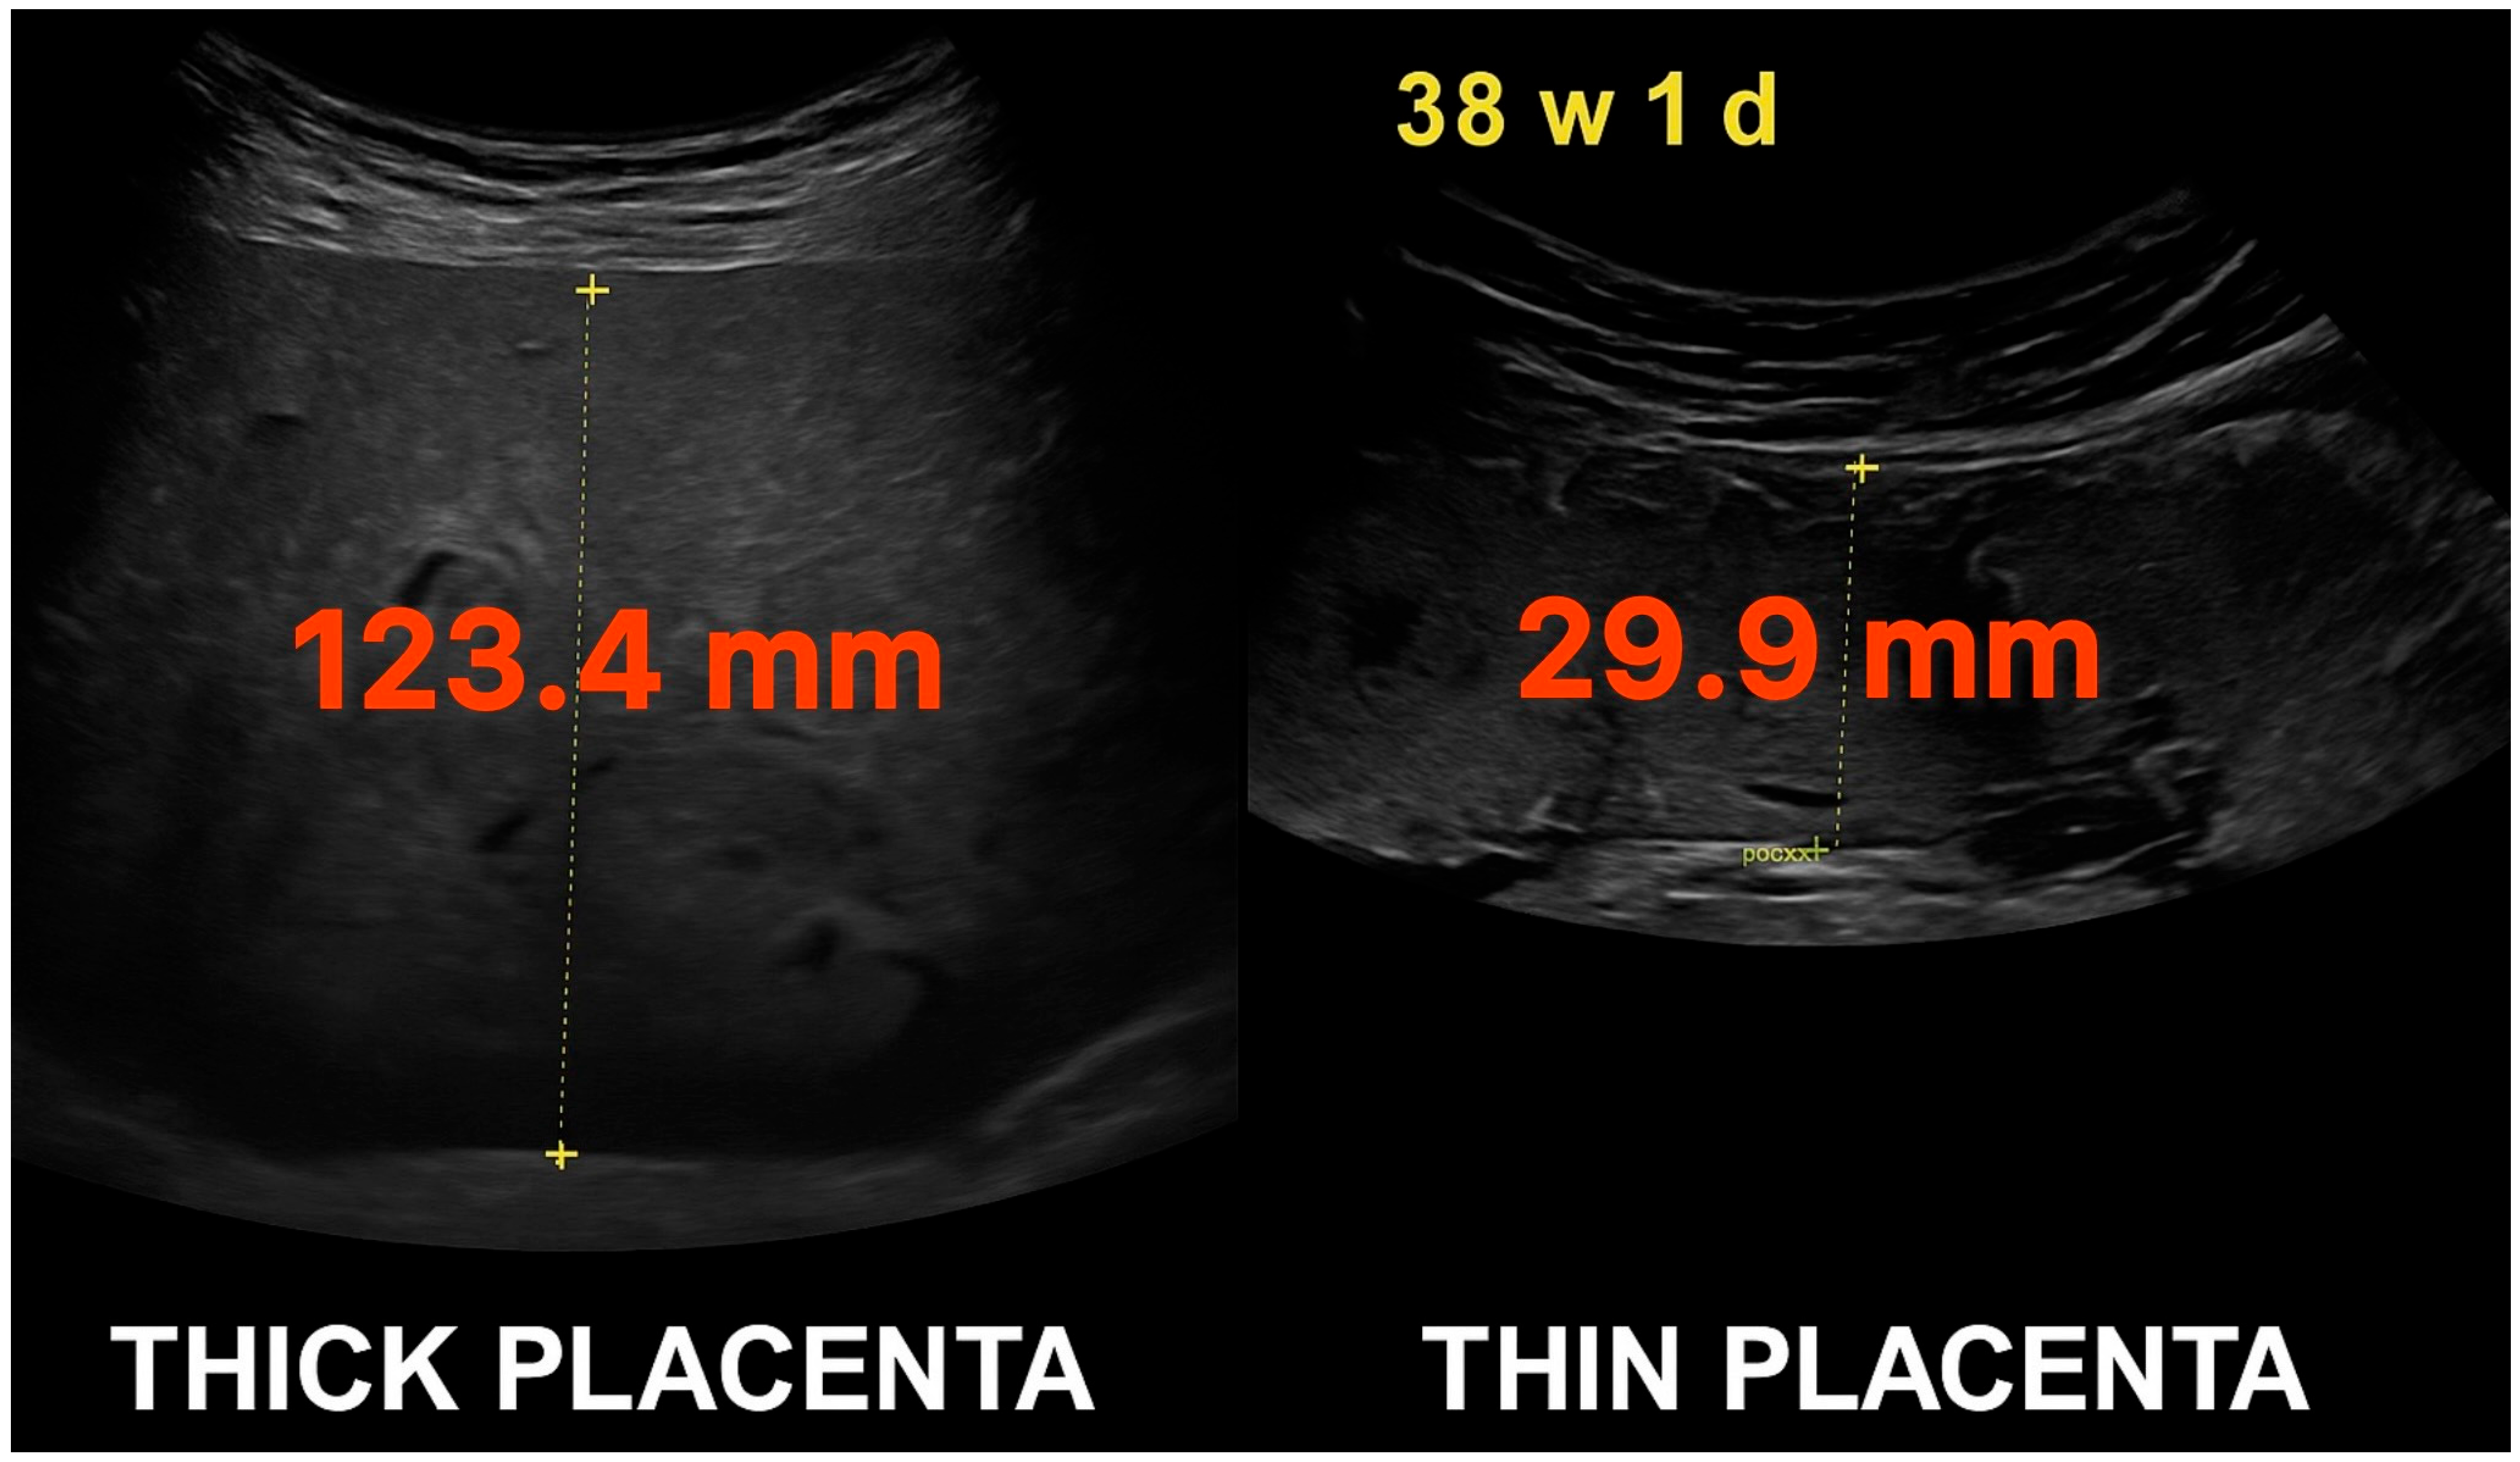

| Placental Thickness (PT) | The maximum perpendicular measurement of the placenta from top to bottom edge on ultrasound, excluding cord insertion. Reported in millimeters (mm). |